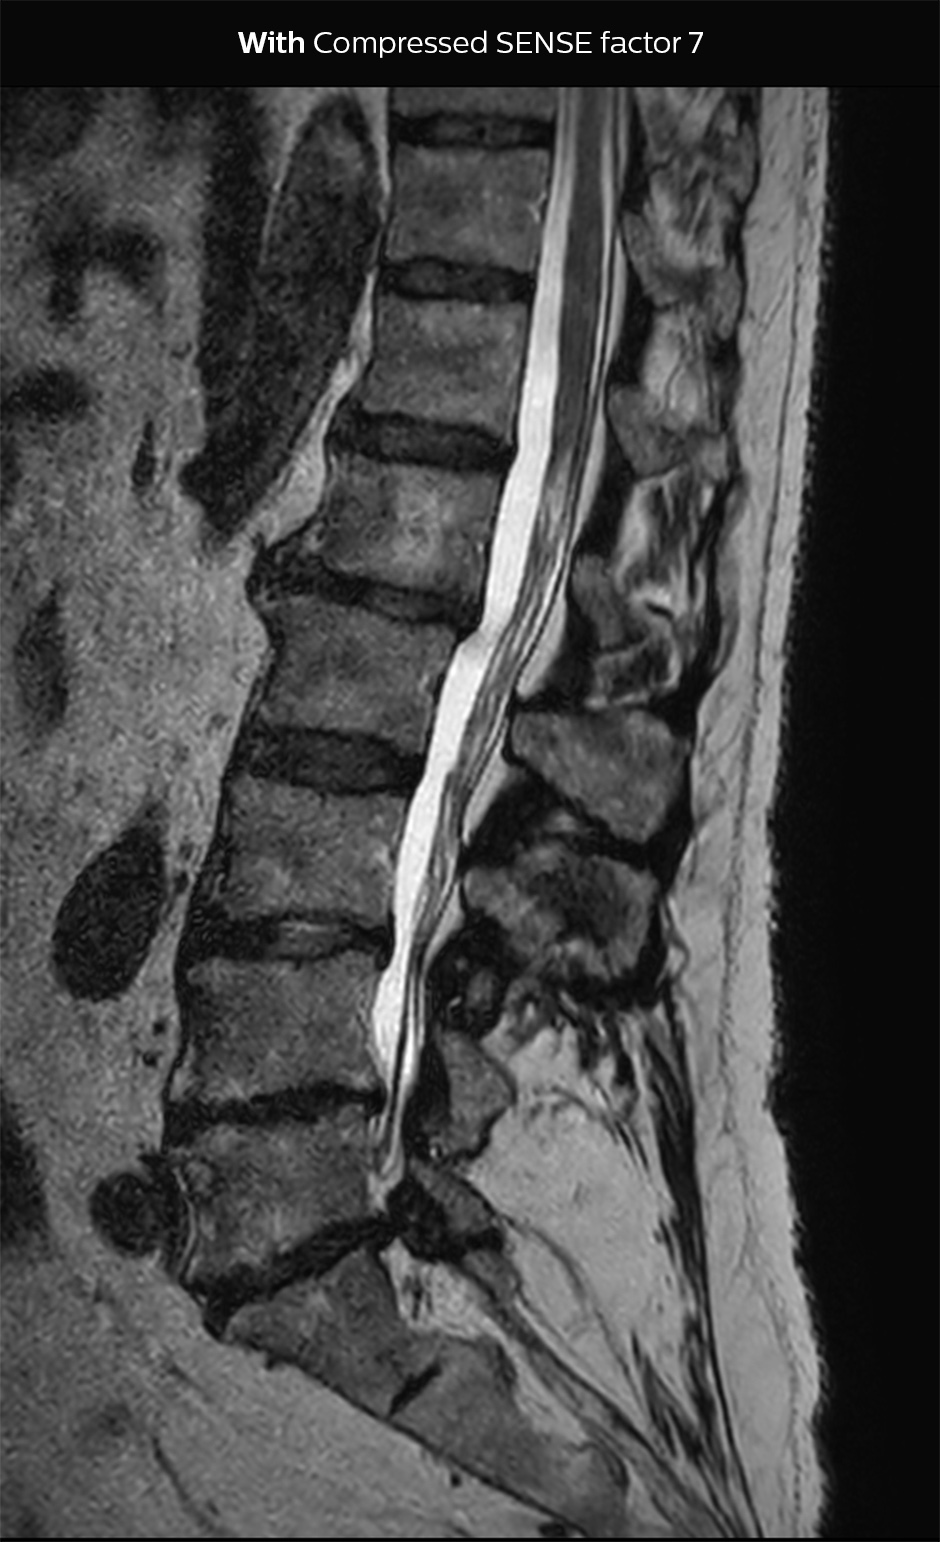

“Our aim for the spine is to use Compressed SENSE to help us make the switch to using 3D SpineVIEW. In lumbar spine, for example, we can reduce scan time for 3D T2W SpineVIEW by 27% to 4:46 minutes, voxel size 0.8 x 0.8 x 1 mm."

“In the end, we would like to just perform a 3D T2W, and 3D T1W, and a STIR T2W for cervical and lumbar spine imaging, and then do secondary reconstructions. That’s why we need high resolution for the 3D sequences, and combining with Compressed SENSE then helps to reduce scan time. In this way, replacing the 2D sequences with 3D sequences is much better for the patient, because we can reduce the time of the scan. Another advantage is that if sometimes a scan is not done properly, we have more freedom to do reconstructions afterwards with the 3D sequences and still make a confident diagnosis from the exam.”

In this example Compressed SENSE has a 26% shorter scan time and improved spatial resolution simultaneously.

3D T2 SpineVIEW, scan time 6:29 min, voxel size 1 x 1 x 1.4 mm

3D T2 SpineVIEW, scan time: 4:46 min, voxel size 0.8 x 0.8 x 1 mm